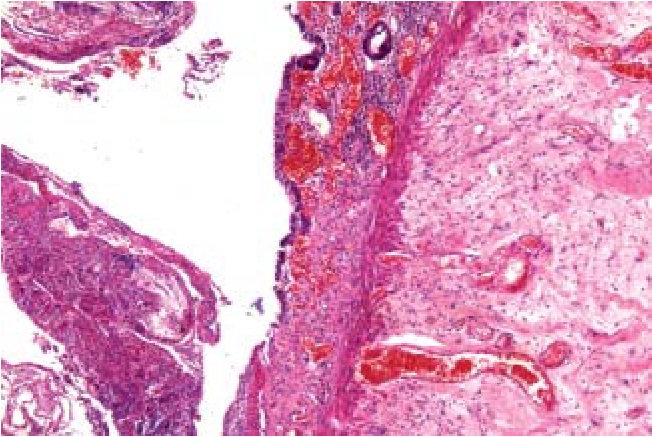

Наиболее характерным для острых перфоративных язв тонкой кишки было первичное повреждение слизистого слоя с развитием множественных некрозов эпителия (рис. 4, 8) на фоне массивной нейтрофильной инфильтрации (рис. 4–8) и значимых гемоциркуляторных расстройств в виде резкого полнокровия и тромбозов сосудов, а также геморрагического пропитывания как слизистого, так и подслизистого слоев (рис. 5, 7, 8), массивного разрастания в подслизистой основе грануляционной ткани (рис. 6) с исходом в фиброз и липоматоз (рис. 8).

Рис. 6. Участок язвы тонкой кишки: разрастания грануляционной ткани, некрозы, нейтрофильная инфильтрация. Окраска гематоксилин – эозином, ув. ×40